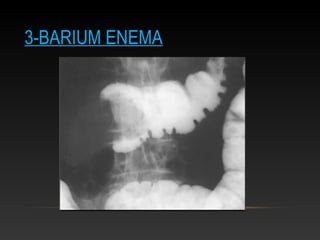

3-BARIUM ENEMA

• Types of enemas

 Pneumatic (air enema)

 Hydrostatic (fluid enema)

 Barium Enema (fluid with contrast)

Barium Enema: